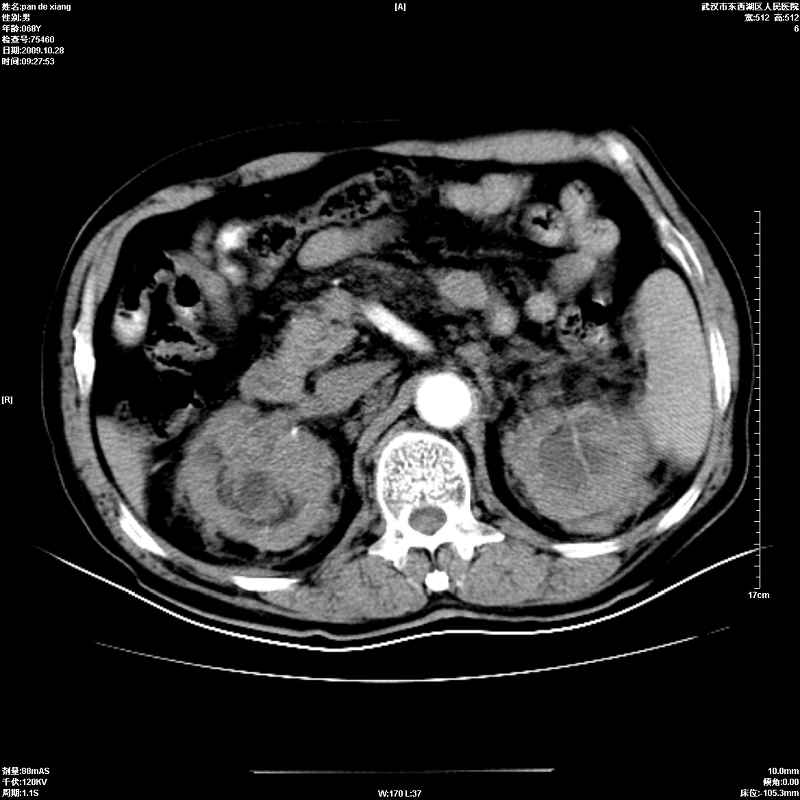

以下是引用杀毒软件在2009-10-28 20:41:00的发言:[br]结合临床考虑---白血病双肾改变或淋巴瘤。

以下是引用zxl51642在2009-10-29 9:59:00的发言:[br]结合临床“单克隆免疫球蛋白血症”,考虑双肾为继发损害并肾功能不全(尿中大量igg及少量iga、igm等大分子免疫球蛋白滤出所致继发损害),椎前软组织肿块为髓外造血。与浆细胞瘤有区别,平扫时有战友说的很清楚。